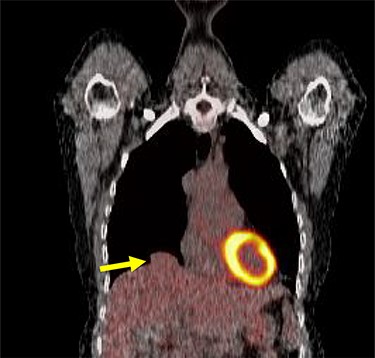

A 54-year-old female without prior thoraco-abdominal trauma presented to the office with two right lower lobe lung nodules. The nodules were initially noted incidentally on a computerized tomography (CT) scan in August 2009 and measured 1.5 cm × 2.8 cm and 0.9 cm × 1.3 cm (Figs 1 and 2). A follow-up CT scan and positron emission tomography (PET) performed in 2010 demonstrated that the nodules were stable in size. The patient was lost to follow-up until March 2019 when she had a CT scan for concern for pneumonia. On these images, the lung nodules had increased in size to 2.8 cm × 4.1 cm and 1.1 cm × 1.4 cm. The patient was otherwise asymptomatic. A PET scan was obtained which showed hypermetabolic nodules with maximum SUV of 3.29 and 1.4, for the larger and smaller nodule, respectively (Figs 3 and 4). Radiographic appearance as well as the growth pattern was consistent with low-grade malignancy suspicious for carcinoid tumor. CT-guided biopsy was not feasible because of location of the tumor.